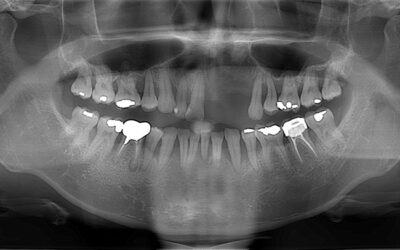

台北胡先生因為長期抽菸的關係,導致他年紀輕輕就面臨嚴重的牙周問題。他的口腔狀況十分嚴峻,口內幾乎所有牙齒都鬆動,甚至因此導致左上二顆門牙缺牙。這不僅影響了他的外貌,使他總是不敢開口大笑,連吃東西時也無法細嚼慢嚥,經常胃痛。...